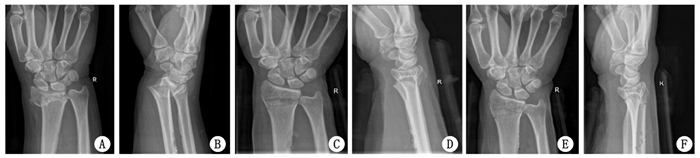

2 结果重复整复后的掌倾角、尺偏角、桡骨长度, 明显好于治疗前及首次整复后, 差异具有统计学意义(P < 0.05), 见表 1.所有患者获得随访, 骨折均愈合, 无神经及血管损伤, 无骨筋膜室综合发生.治疗后6个月, Gartland-Werley腕关节评分, 优14例, 良17例, 可3例, 差1例, 优良率达到88.57%. Knirk-Jupiter关节炎分级评价, 0级27例; 1级5例; 2级2例; 3级1例.典型病例修复前后X线片见图 1~3.

| A、B为治疗前, C、D为首次复位后, E、F为再次复位后 图 3 男性13岁患儿, 右侧桡骨远端骨折治疗后骨折复位变化 |